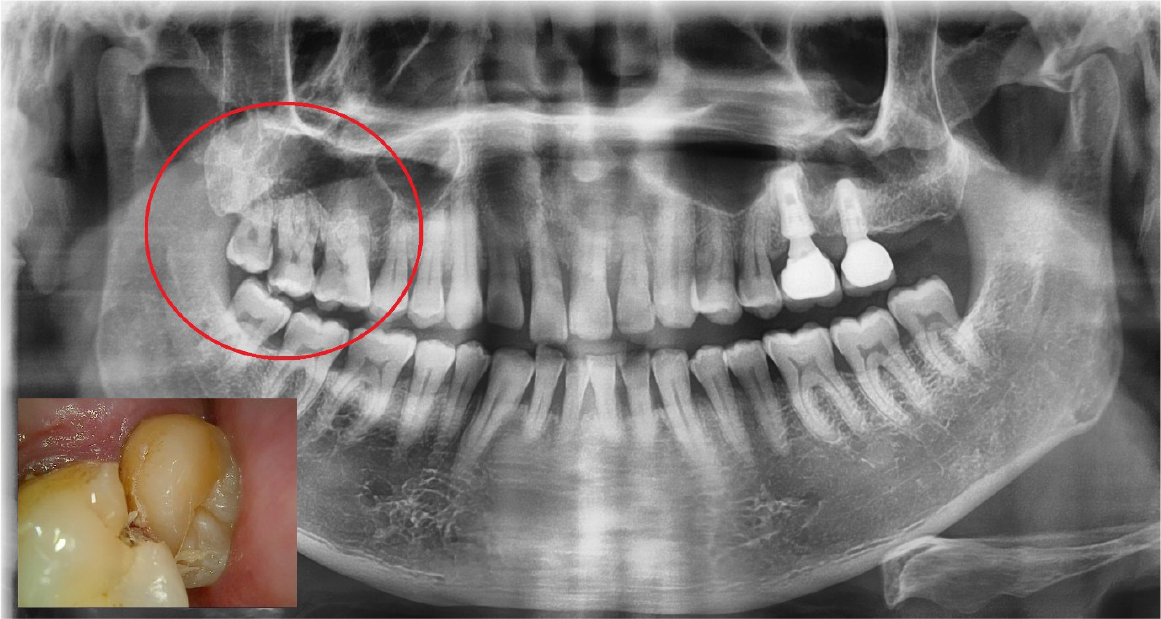

A 64-year-old man presented with a history of the severe pain and food packing of the right maxillary second molar. Clinical and radiological evaluation revealed a root caries of the right maxillary second molar (Fig. 1). The patient had the history of controlled hypertension and he was a heavy smoker (about 1 pack per a day). It was diagnosed with cemental caries on the right maxillary second molar and the immediate implant placement with sinus lift (window approach) was scheduled under local anesthesia because of gaining primary stability through inter-septal bone and the inferior wall of the sinus. Local anesthesia was carried out with 2% lidocaine containing 1:100,000 epinephrine (Huons Co., Seongnam, Korea). One vertical incision was made at mesial end of the horizontal incision.

The right maxillary second and third molars were extracted. A lateral bony window was prepared, and the sinus membrane was thoroughly lifted from the sinus floor with bony window lifted upward and inward. But the mesial aspect of the lifted sinus membrane was perforated (about 4 – 5 mm). A collagen wound dressing (Colla-tape®; Zimmer Dental Carlsbad, CA, USA) was used for the repair of the sinus membrane perforation (Fig. 2). Alloplastic bone-grafting material (A-oss®; Osstem implant Co., Seoul, Korea) was packed and the implant placement (Superline®; Dentium implant Co., Seoul, Korea) was performed (Fig. 3). After 7 days, the patient had pain, nasal discharge and foul odor on the right paranasal area. Under local anesthesia, the flap was elevated. The infected bone material, fixture, collagen wound dressing and infected tissue were removed (Fig. 4). Sinus irrigation was performed for about 5 minutes, until the foul odor and the blockage of ostium disappeared. During this procedure, the size of perforation got bigger by about 1 cm.